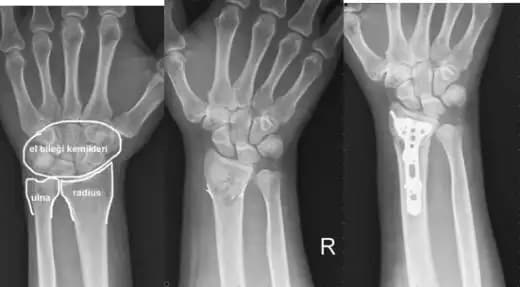

Tanı koymada en etkili yöntemler arasında röntgen ve bazen MRI yer alır. Bu görüntüleme teknikleri, kemik yapısındaki mikro çatlakları ve kırıkların boyutunu net bir biçimde gösterir.

Cerrahi Müdahale: Çok ciddi çatlaklarda veya kemik kayması durumunda gerekebilir. Bu durumda, kemik parçaları uygun pozisyonda sabitlenir.